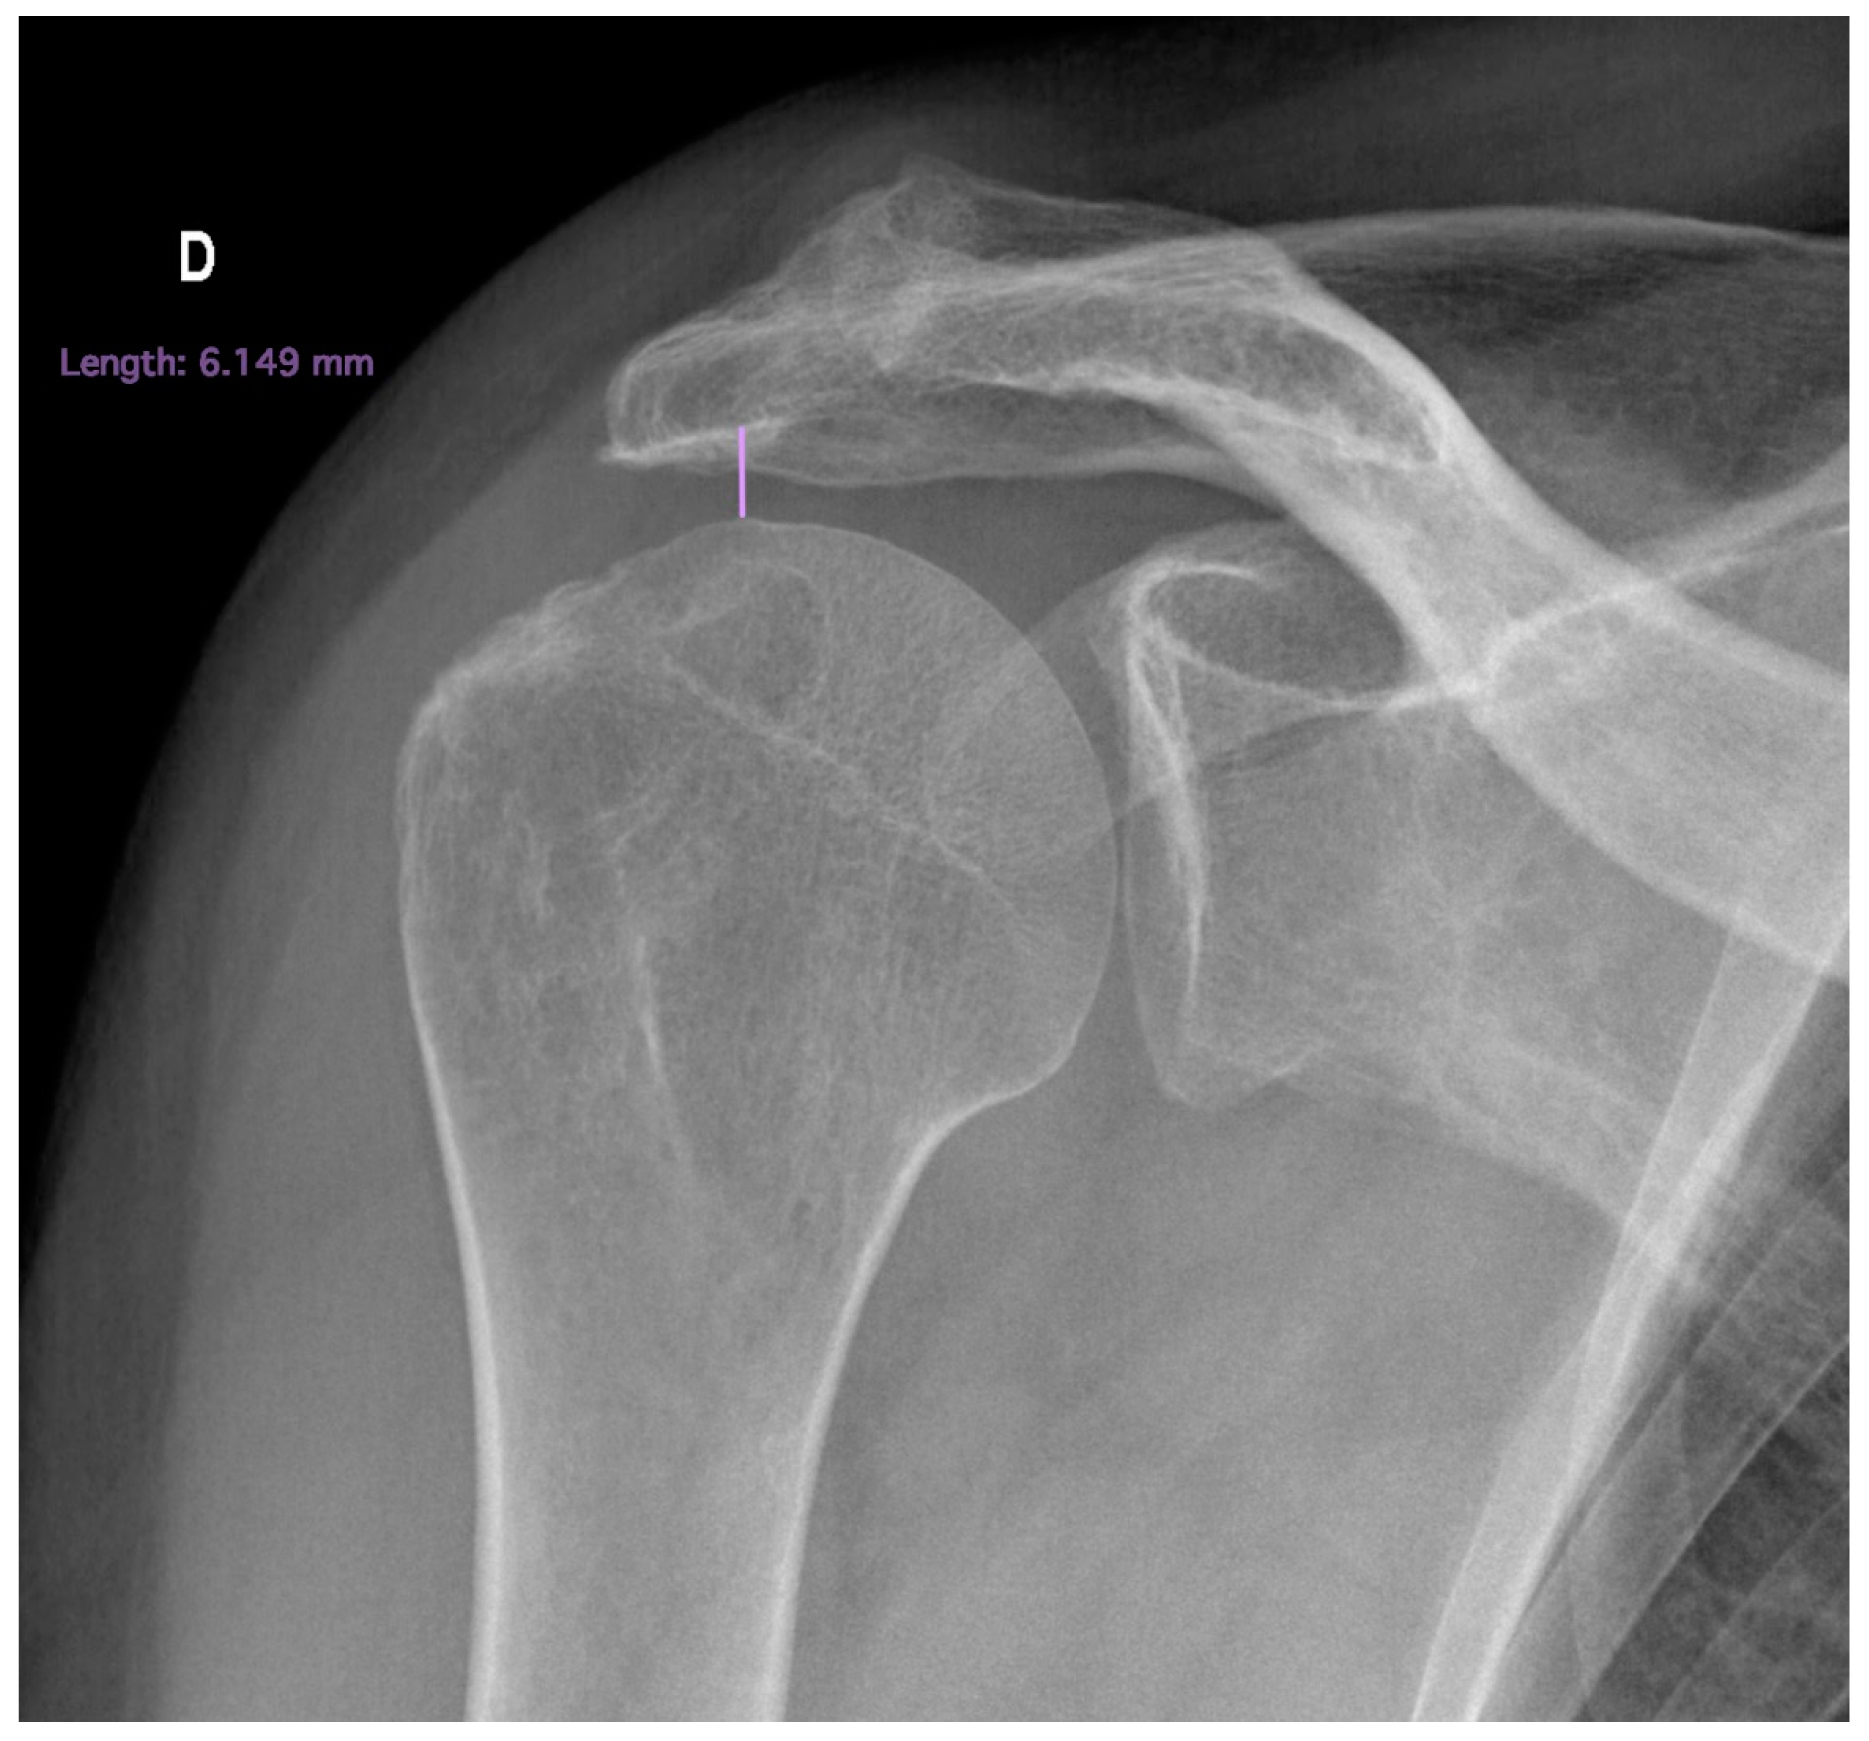

- Acromiohumeral distance

- 4.